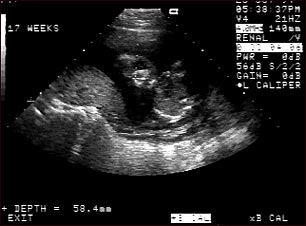

Ultrasonido de un feto normal; cara

Ultrasonido normal de un feto realizado a las 17 semanas de gestación. El rostro fetal se puede observar al centro de la imagen; la cabeza se encuentra doblada a la izquierda, hacia la placenta, la cual se puede ver como un montecillo al lado izquierdo del ultrasonido. Ambos ojos son visibles y el área blanca en el ojo es el cristalino. Otras características faciales como la nariz y la boca también son visibles.